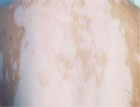

白癜风部位很多,背部,是易患白癜风的一个部位,背部虽然并不像手部、面部、颈部那样常曝露在外,但背部也易受到外界的刺激,造成白癜风的诱发。

背部白癜风通常表现为白斑数目不定,并且,还局限于身体某个部位或某一神经节段等,背部白癜风很少出现自己痊愈的现象,背部患白癜风后,患者必须要到正规的白癜风医院进行诊断才会康复。

背部出现白癜风,不易被人察觉,还容易导致白癜风复发,这些都是背部白癜风难以成功治愈的重要原因。不少背部白癜风患者的白斑除了会造成皮肤损害外,还会累及部分粘膜。

【主要病情】:患者5月前无明显诱因 后背部 出现小片状浅白斑,后扩大、增多,现 胸前、双锁骨、双肩部 均见片状浅、瓷白…【详细】